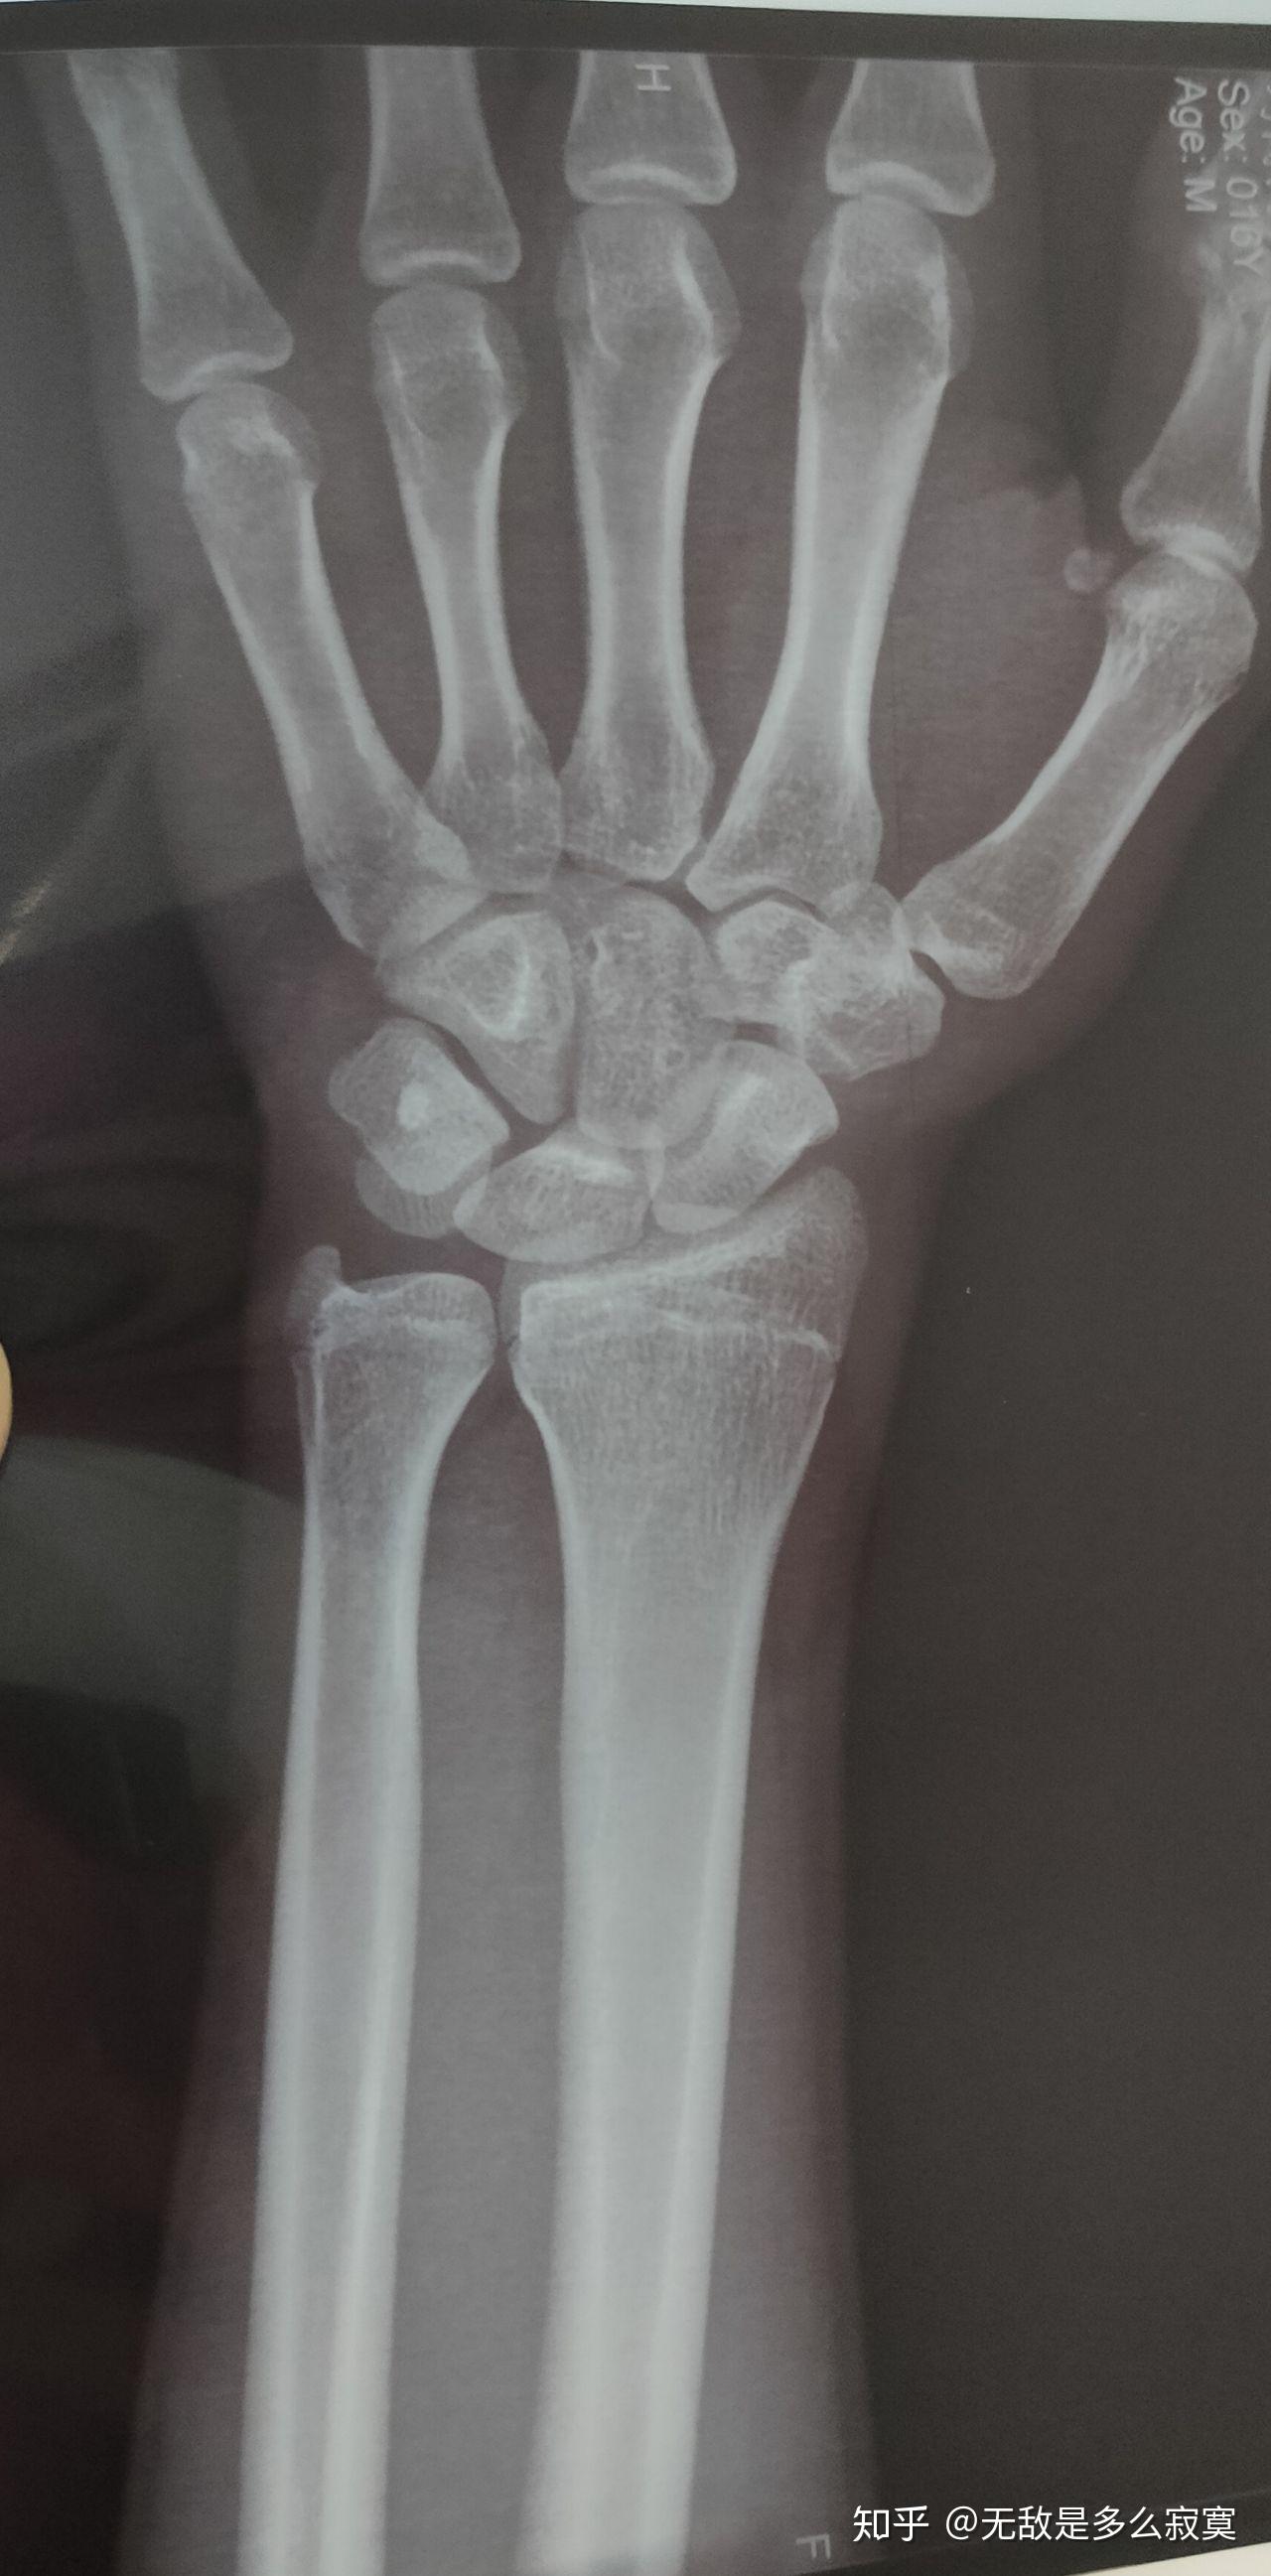

骨骺线接近闭合图

刚刚12岁的儿子, 骨龄已经15岁了,骨骼线也已经快要闭合

手掌骨骺线闭合区别图 第1页

骨骺线接近闭合这么看

骨骺线闭合示意图